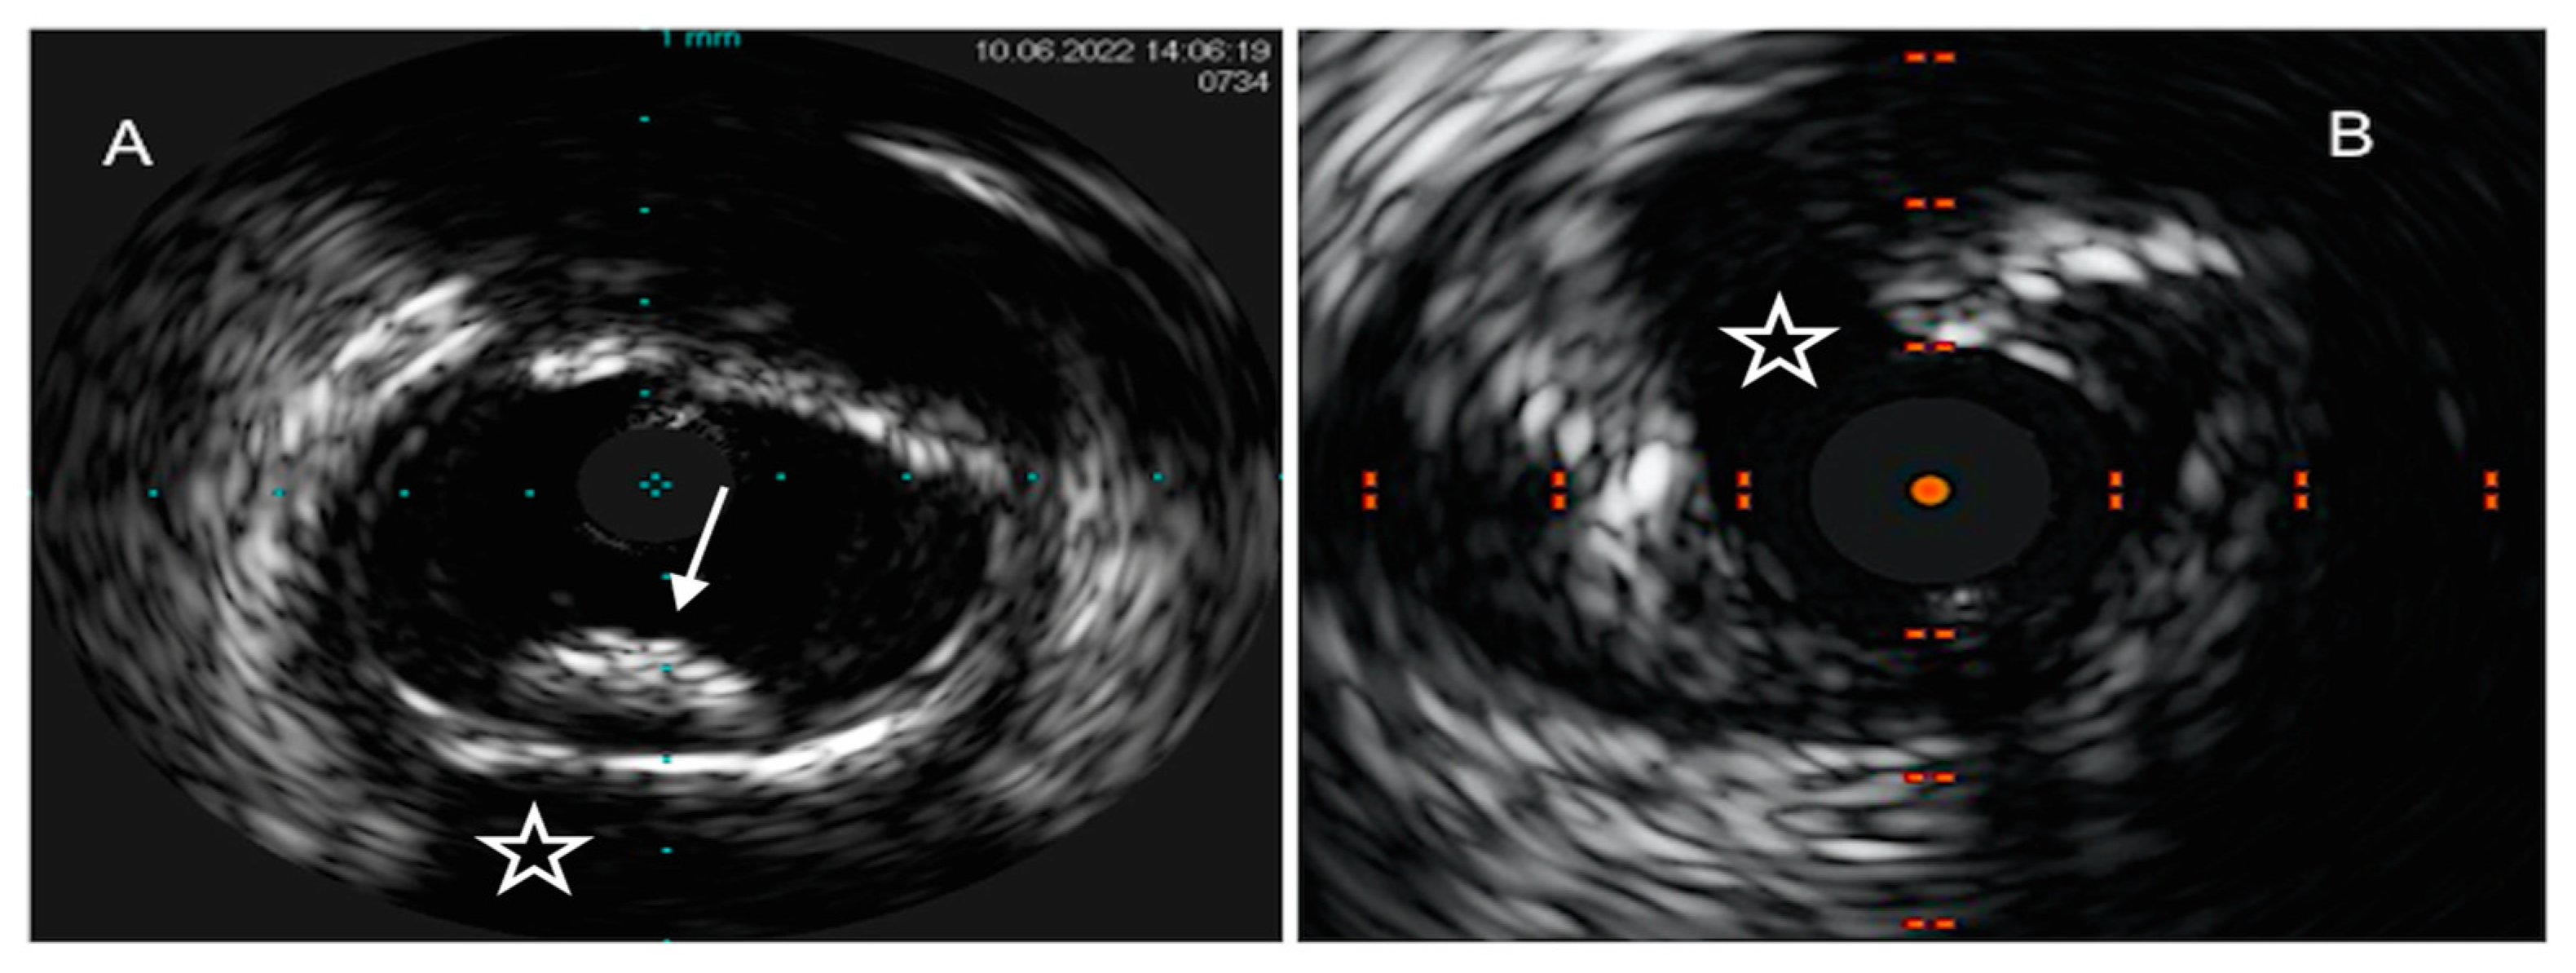

Virtual-histology IVUS (VH-IVUS), by means of radiofrequency ultrasound backscatter data and a color-coded map, was able to overcome these pitfalls, leading to a classification of coronary atherosclerotic plaques into four phenotypes with high diagnostic accuracy as compared to matched histopathological results: calcified and fibrous plaques are recognized as hyperechoic and homogenous structures, marked in white and green, respectively, on the color-coded map, while lipidic and mixed/fibro-fatty plaques were labeled as low-density regions, with a red and yellow appearance, respectively [39] (Figure 1).

Figure 1. IVUS images of coronary plaque phenotype. (A) Example of a calcific plaque, depicted as a bright leading circumferential structure ((A), white arrow) with deeper shadowing ((A), white star). (B) Example of predominantly fibro-fatty plaque, depicted as a structure showing less echogenicity than the surrounding adventitia with a spotty calcification ((B), white arrow), characterized by a focal hyperechoic signal and deeper shadowing.